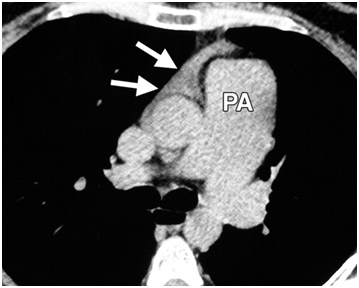

Figure 4: Axial unenhanced CT image obtained in a 58-year-old man with rheumatoid arthritis shows diffuse right pleural thickening with a small amount of pleural effusion (arrows). Diffuse thickening of the pericardium is also seen. High-resolution CT images (not shown) obtained with lung window settings showed no substantial pulmonary abnormalities .